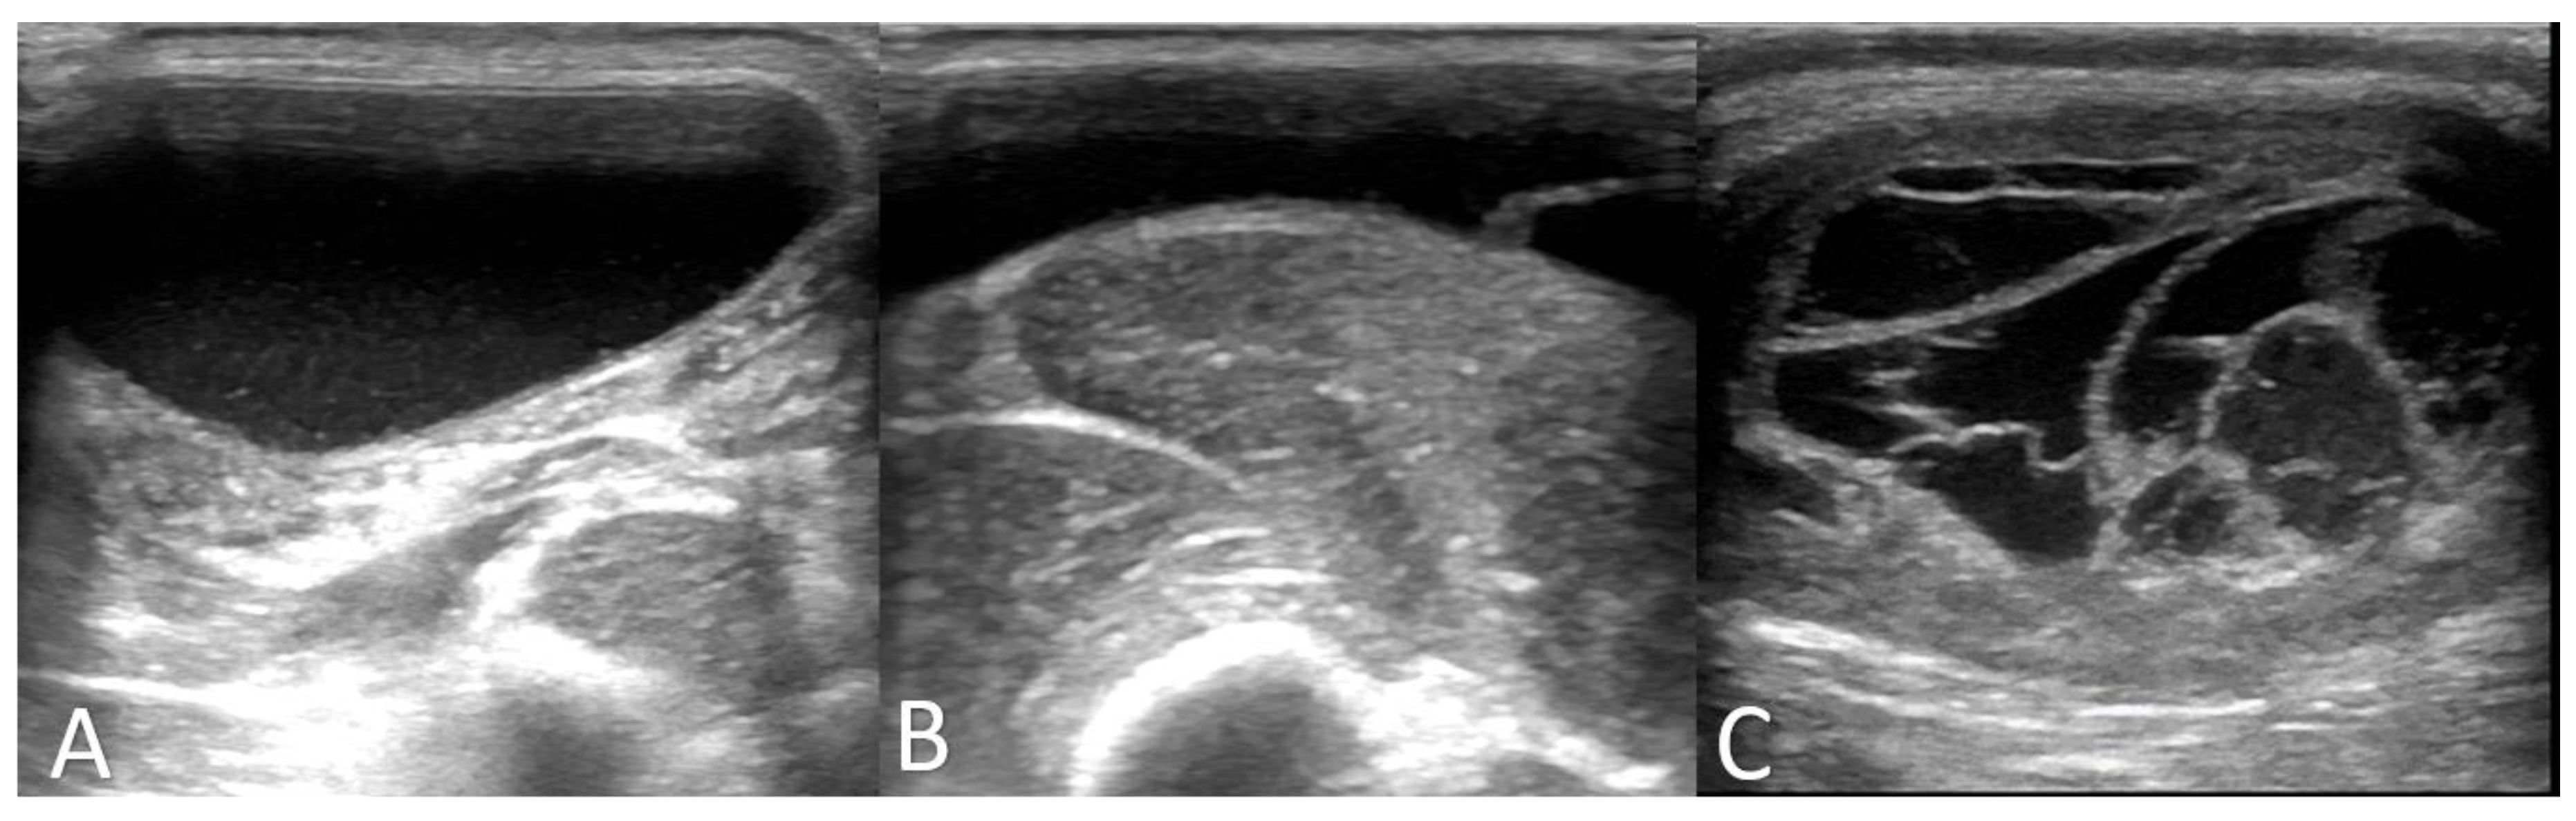

3.1. Clinical and Further Examination